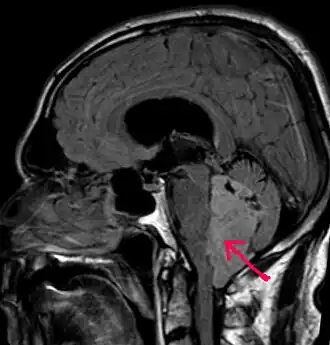

В типичных случаях на МРТ эпендимомы видны в виде объёмных образований, которые заполняют, а иногда и полностью тампонируют полость IV желудочка и распространяются в большую затылочную цистерну или боковую цистерну моста. Солидная часть новообразования на Т1-взвешенных томограммах выглядит изо- или даже гипоинтенсивной и гиперинтенсивной на Т2-взвешенных томограммах[24].

Дифференциальная диагностика эпендимом с другими глиомами основывается в основном на их локализации и топографии, а не на различиях интенсивности сигнала или степени контрастного усиления[25]. Кистозный компонент имеет гипоинтенсивный сигнал на Т1-взвешенных МРТ и гиперинтенсивный по отношению к мозгу на изображениях, взвешенных по Т2. Гетерогенность структуры опухоли обусловлена наличием кист, петрификатов, опухолевой сосудистой сети. После введения контраста отмечается негомогенное усиление средней интенсивности[26]. Дифференциальную диагностику эпендимом боковых желудочков необходимо проводить с медуллобластомами и астроцитомами[23].